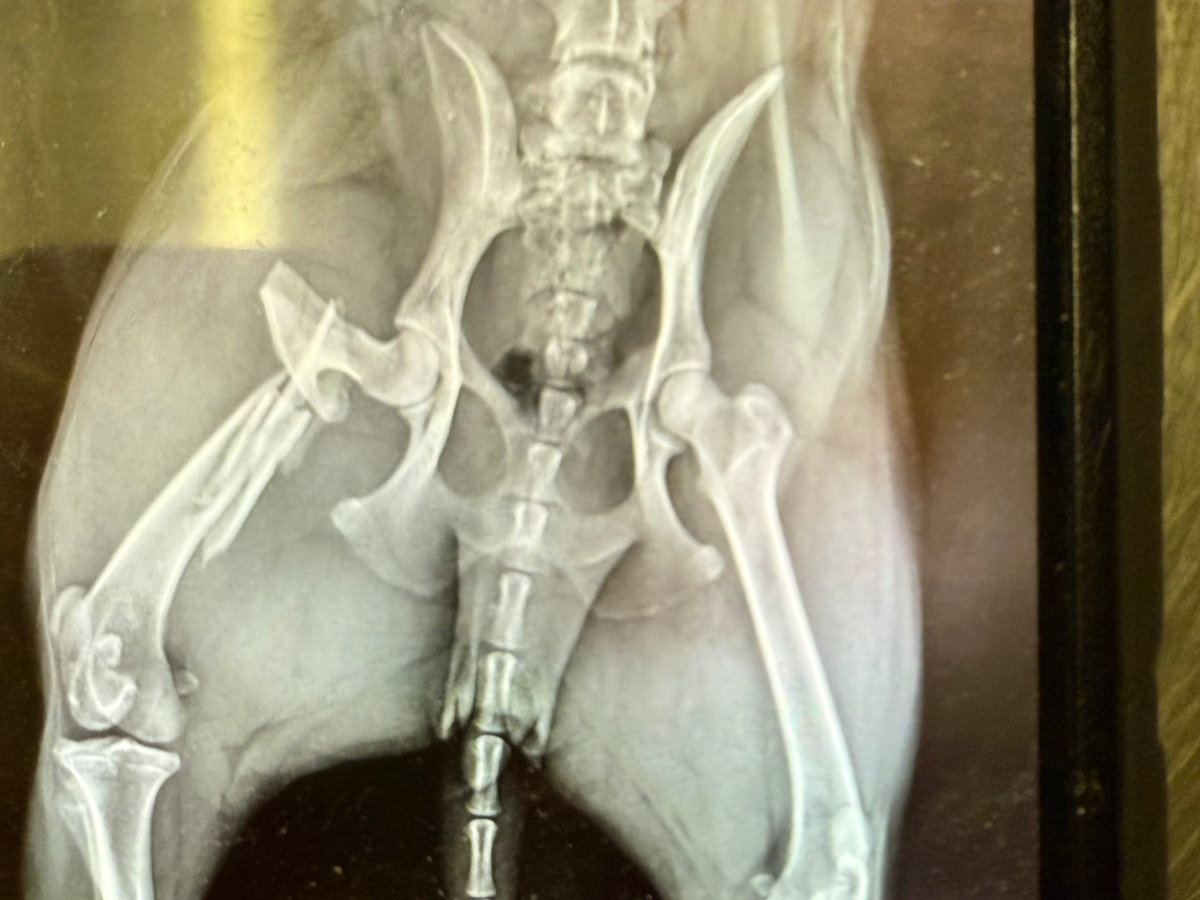

Our dog Mira was unexpectedly run over this morning. It shattered her leg, and we're just thankful that she's still alive. She has to be at Cross Lanes Veterinary Hospital at 8 am tomorrow, and they said at minimum it will be $2,500. She will need surgery to try and fix her leg. A driver ran the stop sign and ran right over her, never stopped, and never tried to let anyone know. He says it's the dog's fault, but we just want to give her the chance to get better.